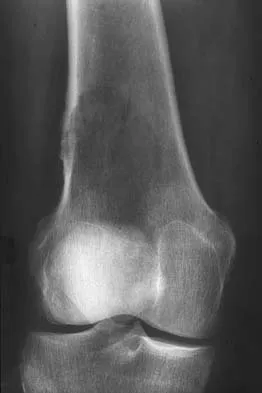

A 68-year-old man with no significant medical history underwent a total knee arthroplasty 4 years ago. A radiograph is shown in Figure 55. He reports that he had no problems with the knee until 6 weeks ago when he noted the gradual onset of pain following a colonoscopy. Examination reveals a painful, swollen knee. Knee aspiration reveals a WBC count of 40,000/mm3. Management should consist of

The treatment of choice for a late hematogenous infection is two-stage resection arthroplasty and reimplantation, with parenteral antibiotics prior to reimplantation. This is particularly true when septic loosening has occurred as in this patient. Open irrigation and debridement with polyethylene exchange has been used successfully when the duration of symptoms is 3 weeks or less. Long-term suppressive antibiotics are most commonly used when the patient's medical condition precludes further surgery. Delayed reimplantation has been shown to be superior to immediate reimplantation in multiple studies. Little data support the use of arthroscopic irrigation and debridement. Swanson KC, Windsor RE: Diagnosis of infection after total knee arthroplasty, in Callaghan JJ, Rosenberg AG, Rubash HE, et al (eds): The Adult Knee. Philadelphia, PA, JB Lippincott, 2003, vol 2, pp 1485-1491.